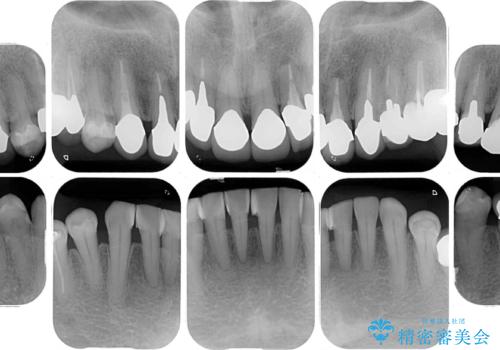

- 抜歯した歯や抜歯が必要と思われる歯を放置したため、奥歯に不快を感じているとのことで来院された患者様です。

右下は奥歯が抜歯したスペースを塞いでしまい、左下はブリッジの支台歯の1つが破折している状態でした。

また、下顎前歯にはスペースがあり、コンポジットレジンでスペースを閉じている状態だったので、前歯のスペースを解消しつつ、奥歯にスペースを獲得するよう矯正治療を行うこととしました。